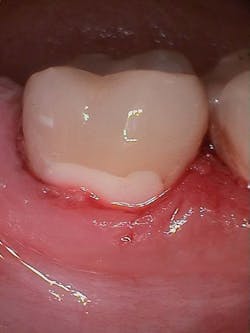

Figure 1 shows a large radiolucency on the mesial and a small radiolucency on the occlusal of tooth 31. Figure 2 shows an initial caries lesion on the distal pit and a leaking occlusal composite. Tooth 31 was sensitive to cold but normal to chewing, bite, and heat. Selective caries removal was used to prevent pulp exposure and preserve the marginal ridge.